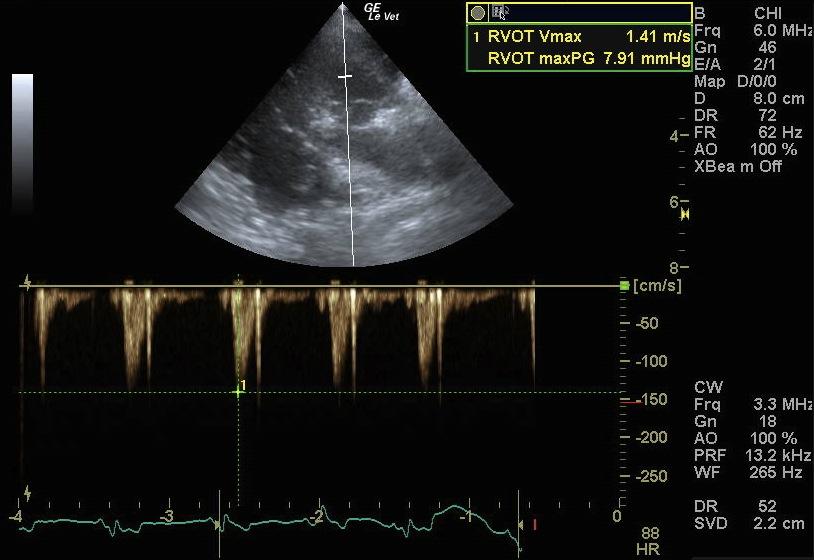

A 9-year-old FS mixed breed dog presented for evaluation of episodic coughing that appeared to be somewhat antibiotic responsive. Survey radiographs showed a normal cardiac silhouette, mild interstitial lung pattern, and an irregular shadow superimposing on the craniobasal cardiac silhouette and adherent to the left thoracic wall from the second to the forth rib. The radiographic changes had been present for almost 2 years.